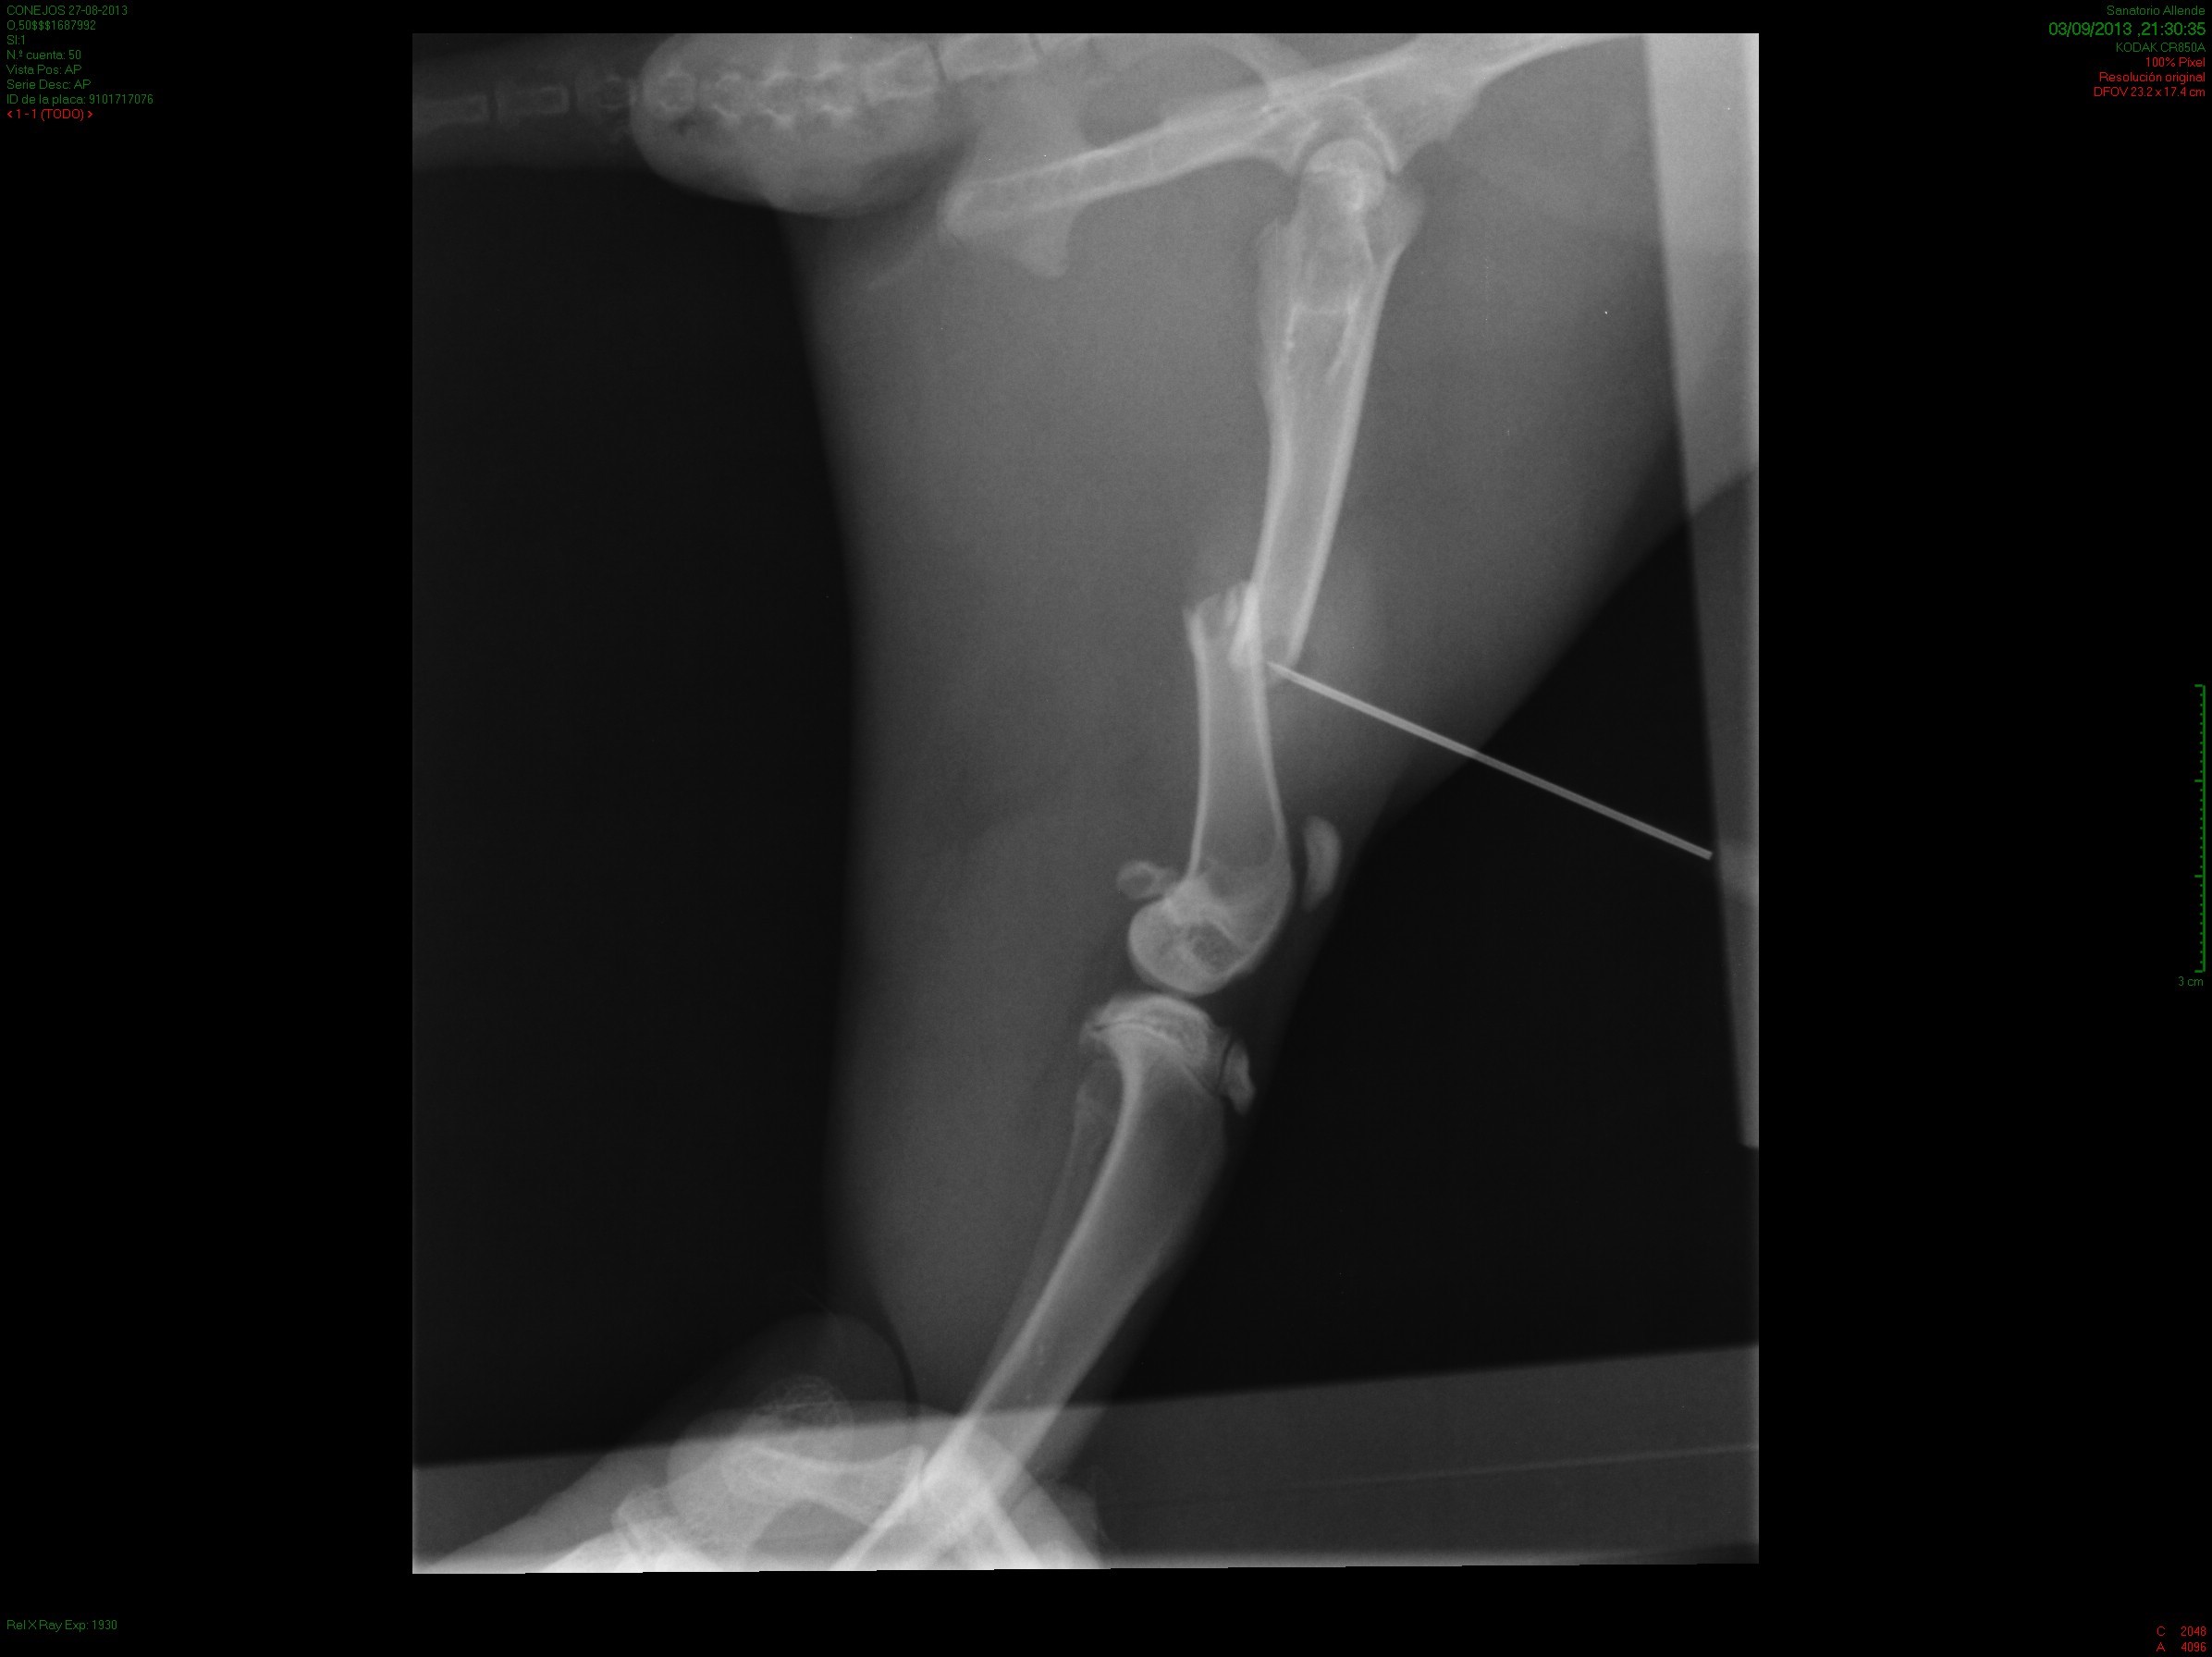

IntroducciónEl objetivo de este estudio experimental fue evaluar el resultado radiológico e histológico de la utilización de alendronato colocado localmente en el foco de fracturas de fémur en conejos.Material y métodosSe utilizaron 30 conejos a los cuales se fracturó el fémur derecho y se distribuyeron en tres grupos de 10 animales cada uno. A los conejos del grupo I se le colocó una solución con alendronato a nivel del foco de fractura, al grupo II se le realizó el mismo procedimiento a los siete días de la fractura, dejando el grupo III como control. Se realizó la evaluación radiográfica al momento de la fractura y a los 42 días del procedimiento. Se evaluó las características de callo óseo mediante anatomía patológica, radiología y tomografía axial computada.ResultadosSe evaluaron 24 conejos, por el fallecimiento de dos conejos del grupo II y cuatro del grupo III. El análisis histológico evidenció moderada formación ósea en los tres grupos sin diferencias estadísticamente significativas (p=0,8336). En cuanto a los resultados evaluados por estudios de imagen no existieron diferencias estadísticamente significativas del tamaño del callo óseo entre los grupos para los dos estudios (p= 0,777 en Rx y p=0,349 en TAC).ConclusiónLos resultados de este trabajo experimental evidenciaron que la utilización de alendronato colocado localmente en el foco de fractura no afectó de manera estadísticamente significativa, histológica ni radiológicamente, el proceso de consolidación en las primeras 6 semanas posteriores a la fractura de fémur en conejos. AbstractIntroduction: The aim of this experimental study was to evaluate the radiologic and histological results of the use of alendronate administered locally at the fractures site in rabbits.Methods: The fractured right femur of 30 rabbits was used for evaluation. The animals were distributed in three groups of 10 rabbits each. A solution with alendronate was placed at the fracture site in group 1; the same procedure was performed 7 days after the fracture in group 2, and group 3 functioned as control. Radiographic evaluation was performed at the time of the fracture and at day 42. Radiological, PA and CT-scan evaluations of bone callus characteristics in each rabbit were performed.Results: Twenty-four rabbits were evaluated (2 rabbits in group 2 and 4 in group 3 died). Histological evaluation evidenced moderate bone formation in the three groups without statistically significant differences (p=0.8336). Concerning imaging studies, there were no statistically significant differences in the size of bone callus among groups for both studies (X-rays: p=0.777 and CT: p=0.349).Conclusion: The use of alendronate administered locally at the fracture site, in the acute period and after one week, did not alter the normal consolidation process determined by PA and radiology, six weeks after femur fracture in rabbits.Descargas